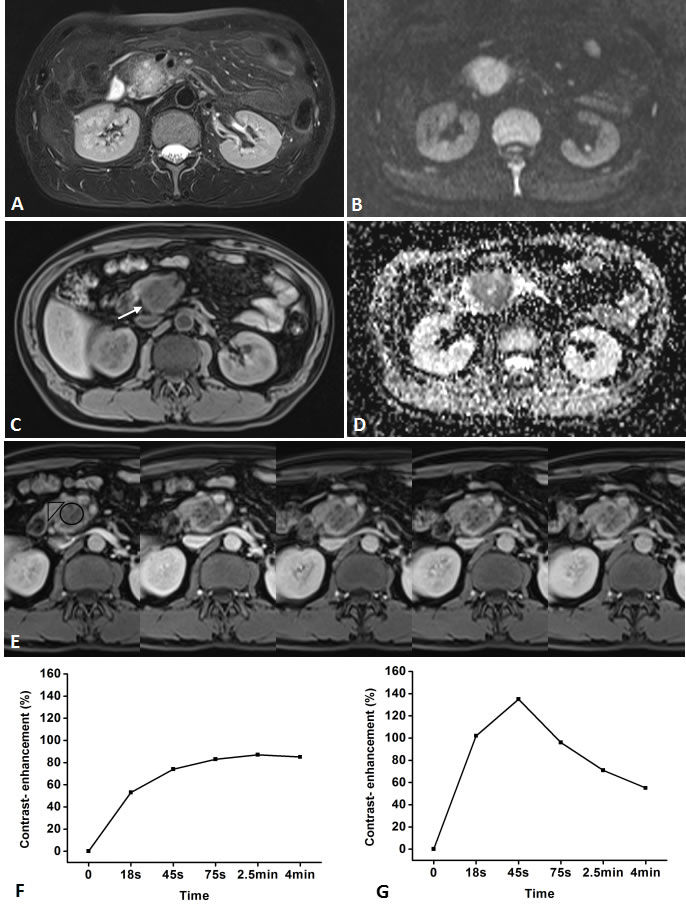

Figure 2: Representative pancreatic T2-weighted image (A), DWI with a b value of 600 s/mm2 (B), T1-weighted image (C), ADC map (D), DCE-MR images (E), and TIC profiles (F, G) in a 49-year-old man with pancreatic carcinoma in the head of pancreas (white arrow). DCE-MR images: 18s, 45s, 75s, 2.5 and 4 min aftercontrast injection with constant gray scale. The ROIs of mass and non-mass adjacent parenchyma (NAP) indicated with black circle and black triangle. Pancreatic mass demonstrates type-IV b TIC which shows a slow, gradually increasing enhancement pattern followed by a plateau, while NAP demonstrates type-II aTIC which shows a rapidly increasing then gradually decreasing enhancement pattern. DWI shows pancreatic mass is clearly seen as hyperintense with a well-defined margin.